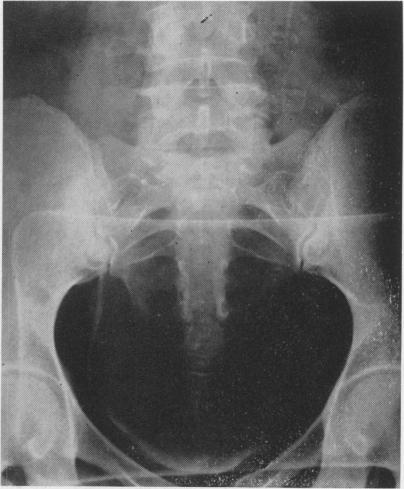

Methods of preventing injury to the ureters and bladder during gynecological operations.

Ann Surg. 1956 Jun;143(6):752-63. doi: 10.1097/00000658-195606000-00004.